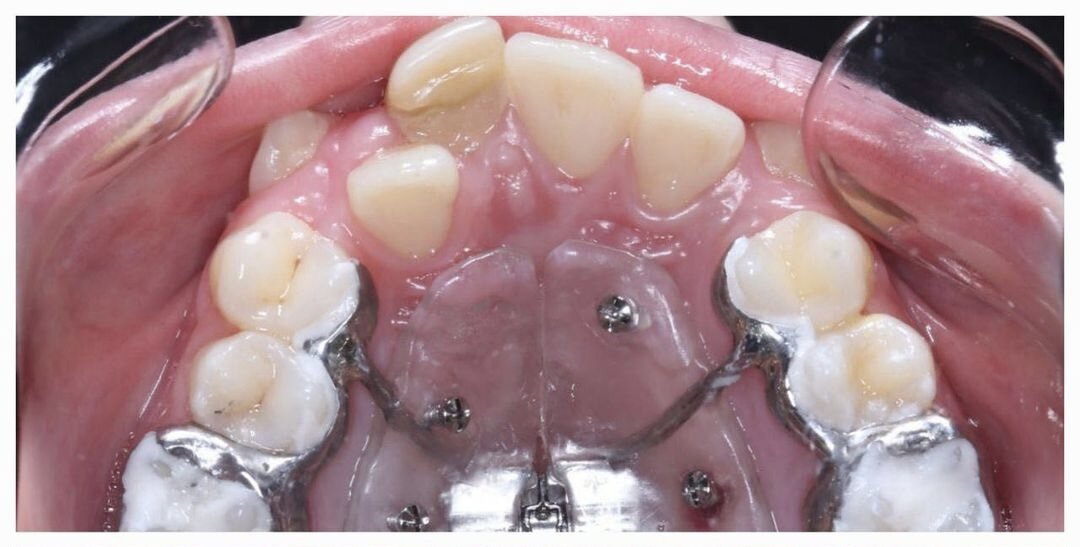

Чтобы избежать удаления премоляров, было принято решение изготовить модифицированный аппарат по типу Марко Роса, ключевое отличие которого - дополнительная фиксация к небу при помощи ортодонтических мини-винтов.

Фиксация аппарата

Наличие такой опоры позволяет наиболее эффективно передавать давление на небный шов, что приводит к его разрыву и скелетному расширению верхней челюсти. В противном же случае, мы получили бы наклон боковых зубов в стороны, а объем кости остался бы практически прежним.